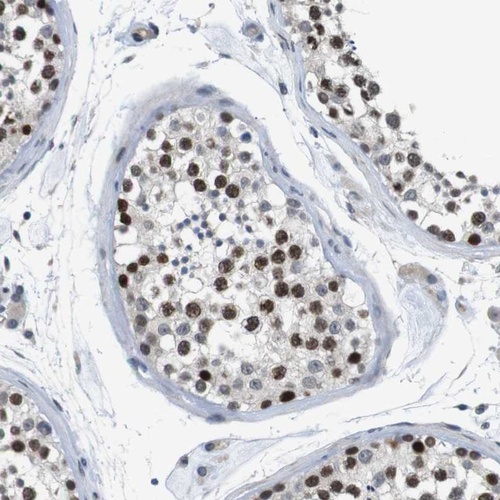

Immunohistochemical staining of human testis shows strong nuclear positivity in cells in seminiferus ducts.